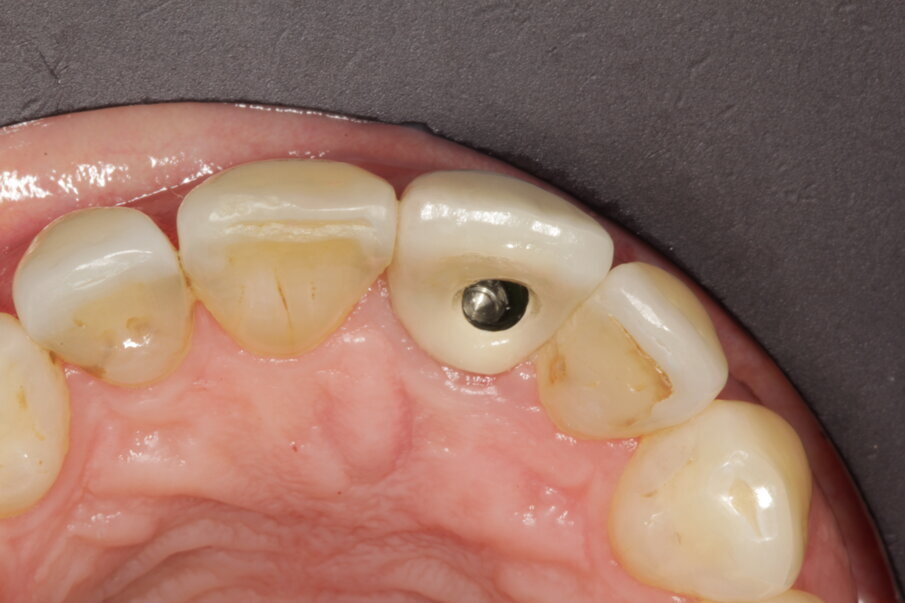

Transfer of the profile

A new intraoral scan sequence was performed. First was the scan of the full arch with the temporary crown in place. The provisional was then removed from the mouth and screwed on to an implant replica fixed to a stable support with wax. The second scan revealed in 360° the modified shape of the temporary crown, including the gingival profile (Fig. 33). These files can be easily matched in the CAD software when the technician designs the definitive crown (Figs. 34–36). If a monolithic material is used, the technician may copy the entire shape of the temporary. When a support is needed that will be layered with ceramic afterwards, at least the gingival profile can be duplicated in a reliable way.